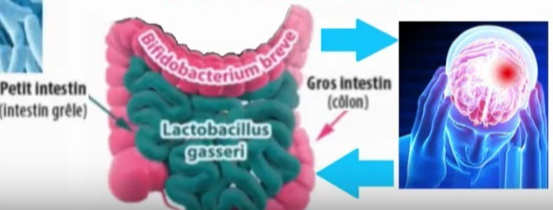

Le système nerveux qui régit l’intestin (système nerveux entérique ou SNE) contient à lui seul 200 millions de neurones. Sa fonction première est d’assurer la motricité intestinale. Par ailleurs, l’intestin est en interaction étroite et bidirectionnelle avec le système nerveux central (SNC). On parle d’un axe intestin-cerveau, à travers lequel les deux organes communiquent. C’est la raison pour laquelle on qualifie le système nerveux entérique de deuxième cerveau.

Le système nerveux qui régit l’intestin (système nerveux entérique ou SNE) contient à lui seul 200 millions de neurones. Sa fonction première est d’assurer la motricité intestinale. Par ailleurs, l’intestin est en interaction étroite et bidirectionnelle avec le système nerveux central (SNC). On parle d’un axe intestin-cerveau, à travers lequel les deux organes communiquent. C’est la raison pour laquelle on qualifie le système nerveux entérique de deuxième cerveau.

Les chercheurs ont très tôt posé l’hypothèse selon laquelle un déséquilibre du microbiote pourrait modifier l’information transmise au système nerveux central et au système nerveux entérique, modifiant ainsi le fonctionnement des deux organes. Les mécanismes impliqués seraient multiples :

- Des composés issus du microbiote (métabolites ou éléments structuraux) peuvent diffuser à travers la paroi intestinale. Ils peuvent directement moduler le SNE, ce qui impactera le fonctionnement de l’intestin, mais aussi le nerf vague: il en découlera alors une modulation du fonctionnement du cerveau.

- D’autre part, ces composés peuvent aussi atteindre le SNC directement, par voie sanguine. Une fois parvenus dans le cerveau, ils peuvent s’avérer délétères pour certaines fonctions nerveuses, tels quels ou après métabolisation.

- Enfin, les bactéries peuvent indirectement moduler certaines fonctions endocrines dont le contrôle est notamment assuré par le SNC : elles ont en effet la capacité à interagir avec les cellules dites entéroendocrines localisées dans la paroi, et qui sont en lien avec le cerveau. Cela a par exemple été décrit pour la voie sérotoninergique.

Ces différents mécanismes soutiennent donc l’idée que la dysbiose intestinale observée dans des troubles du neurodéveloppement ou des maladies neurodégénératives, comme Parkinson ou Alzheimer, peuvent non seulement contribuer aux troubles digestifs dont sont atteints ces patients, mais aussi aux symptômes neurologiques.